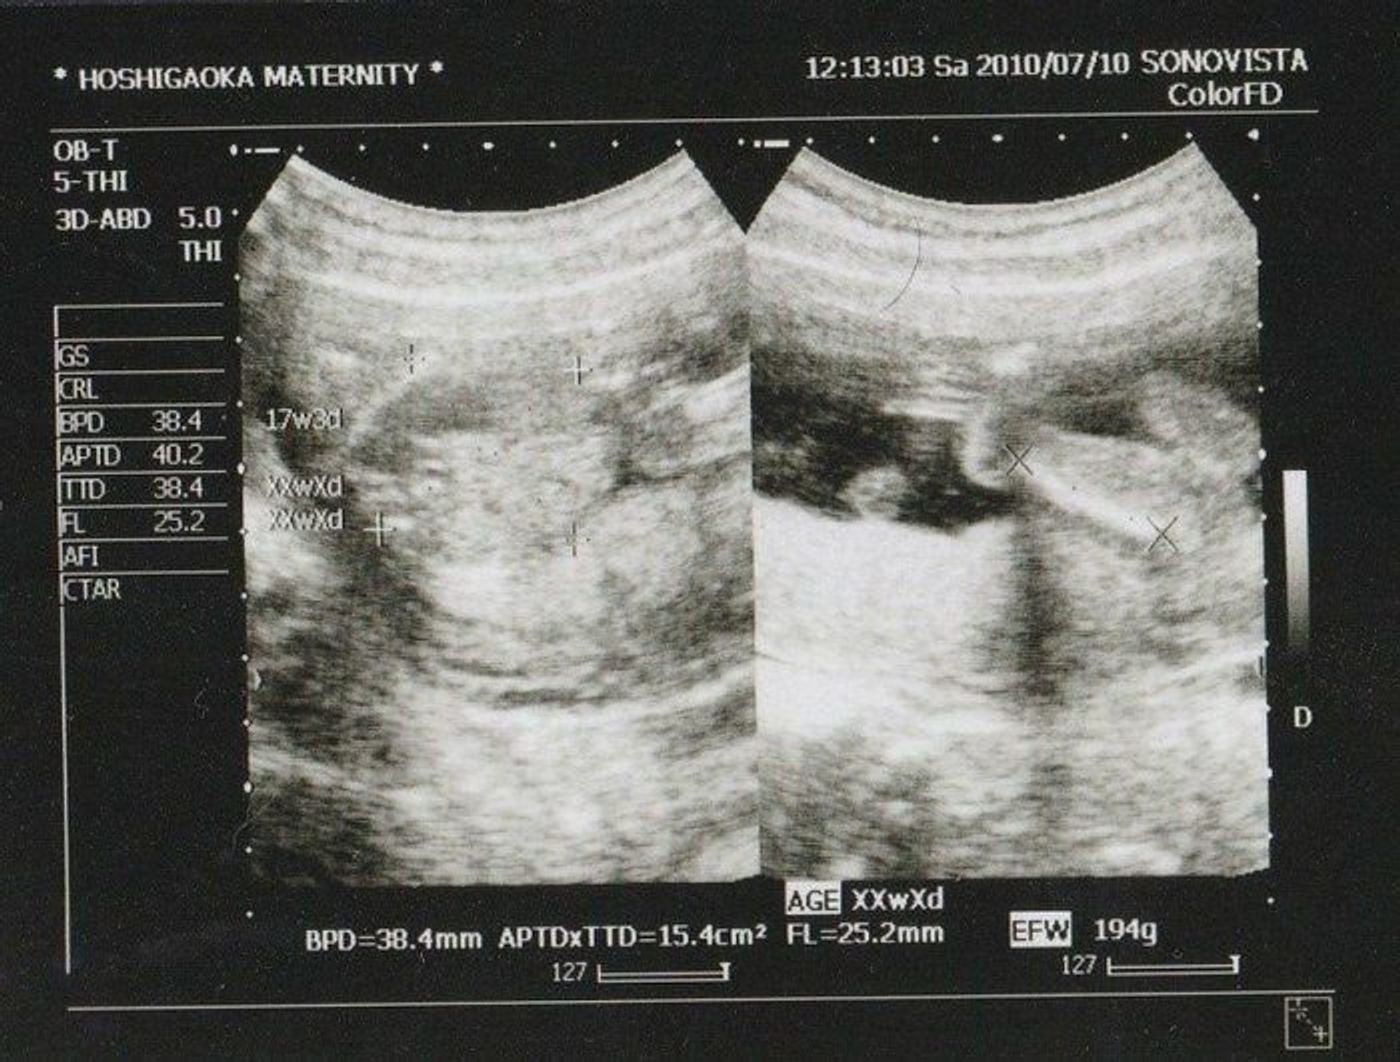

17週 性別 男の子 エコー-15wのエコー 7 妊娠17週目くらいの時にエコー 8 8割方 男の子と言われましたが 9 13週ですがお腹がすごく出ています;Amiさんの妊娠17週目のエコー写真 推定体重は3773g! 骨盤に入らず緊急帝王切開になった長女の成長をエコー写真で振り返る 右側のエコー写真には、お尻と脚が2本写っています。 このエコー検査から「性別は女の子かもしれない」と主治医の先生から言わ

妊娠17週5日 17w5d の超音波 エコー 写真

先週、17週で妊婦検診を受けました。 性別を知りたかったのですが、まだわからないと言われ。 元気であればどちらでも構わないのですが、上が男の子で、もう1人(欲を言えばもう2人)男の子がほしいなぁと思っています。(3太郎希望) が、エコー写真での性別の見分け方について エコー写真で性別を見分けることができます。 赤ちゃんは、だいたい9週目頃に入るとだんだんと男の子、女の子として変化を始めていきます。 ただ、9週目頃では赤ちゃんが小さいため性別の判断はつきません。男の子の性器は股部分に突起として写り 男の子の性別判定はいつから可能? 男の子の性別判定はいつから可能なのでしょうか? 男の子の性別判定は比較的早く、早くて15週・16週ごろからシンボルが見えてくる ようです! 私の場合、1人目の男の子が17週で性別ほぼ確定となりました。

この17週の検診のときでは 「まだ角度とかにもよるから断定は出来ないけど、 女の子の可能性が7割 ぐらいかな」とのこと。 Incoming Term 性別 エコー 女の子, 性別 エコー 女の子から男の子, 性別 エコー 女の子 突起物, 妊娠 性別 エコー 女の子 子宮, 胎児 性別 エコー 女の子, 13週 性別 女の子 エコー, 14週 性別 女の子 エコー, 21週 性別 女の子 エコー, 19週 性別 女の子 エコー, エコー性別判定 男の子のエコー写真 男の子のシンボルが見えやすいエコー写真を集めてみました! ぜひ参考にしてみてくださいね 17週の男の子のエコー写真 左側がお尻、上下に足が見え、その間にシンボル